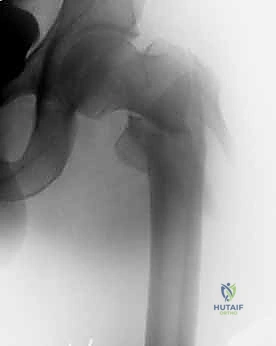

التصوير الطبي المتقدم

- الأشعة السينية (X-rays): هي المعيار الذهبي الأولي. يتم أخذ صور من الأمام للخلف (AP) وصور جانبية (Lateral) للحوض والورك المصاب. تكشف هذه الصور عن موقع الكسر، نوعه (بسيط أم مفتت)، ودرجة الإزاحة.

- التصوير المقطعي المحوسب (CT Scan): في الحالات المعقدة، أو عندما يكون الكسر مفتتاً بشدة ويمتد إلى مناطق أخرى، يطلب الدكتور هطيف صورة مقطعية ثلاثية الأبعاد لبناء خطة جراحية دقيقة للغاية.

مجموعة من الصور الإضافية التي توضح مراحل دقيقة من العمل الجراحي المعقد الذي يجريه الأستاذ الدكتور محمد هطيف لضمان أعلى درجات الدقة الميكانيكية الحيوية: